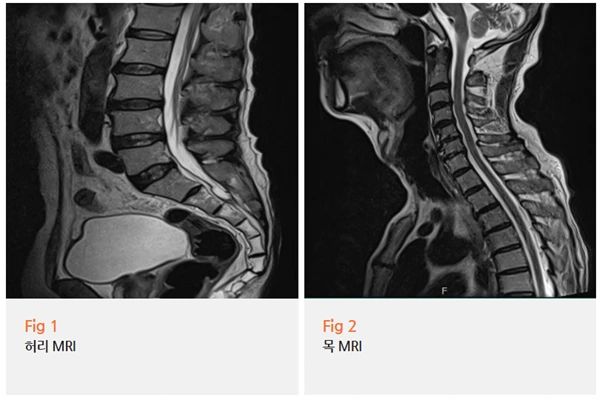

내원 당일 신경과 진료를 통해 MRI와 근전도 검사를 시행했어요.

손가락과 발목 근력이 뚜렷하게 저하되어 있었고,

근전도 검사에서 말초신경 손상 소견이 확인됐어요.

%EA%B7%B8%EB%A6%BC2.png?type=w966

신경과 입장에서 진단의 핵심은 단순히 어디가 저리냐가 아니에요.

저림이 어떤 패턴으로 분포하는지, 근력 저하가 어느 근육군에 나타나는지,

반사 반응은 어떻게 달라져 있는지를 종합적으로 봐야 해요.

이 환자분은 사지 말단부터

대칭적으로 증상이 나타나는 전형적인 말초신경병증 패턴이었어요.

그리고 항암치료 이력과 증상 발생 시점이 정확하게 맞아떨어졌고요.